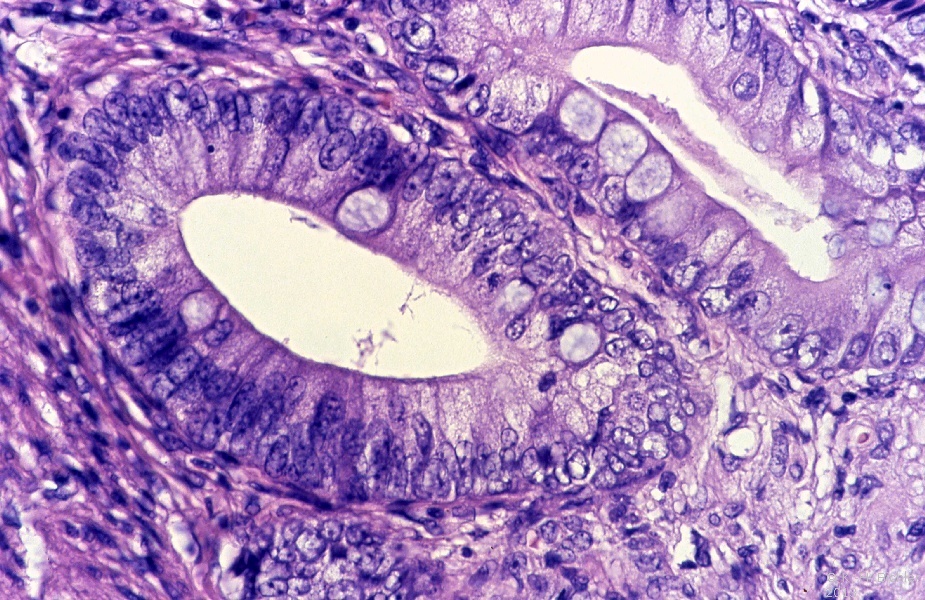

Die histologische Untersuchung der Metastase ergab ein reifes Teratom und Anteile eines embryonalen Karzinoms mit Einbrüchen des Tumors in das Gefäßsystem (Abbildung 7)

Literatur:Ulbright, T. M.: "Neoplasm of Testis", in Bostwick, D.G. und Eble, J.E.: "Urologic surgical pathology", Mosby St. Louis, 1997. Es fanden sich typische Strukturen des reifen Teratoms (Abbildung 7 ab), die zusammenfassend im Schema dargestellt sind (Abbildung 8).